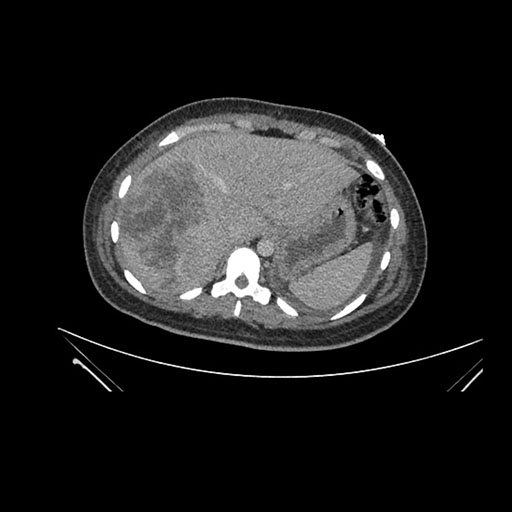

Imaging Analysis

Look through the patient's CT scan to identify any areas of concern for the necessary procedure.

Axial Arterial

Based on initial findings, which issue(s) would you be most concerned about?